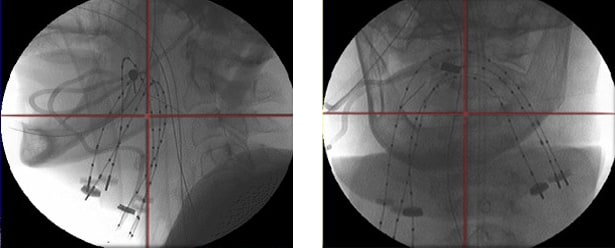

通过X射线、CT或MR成像,获得治疗计划所需的影像数据。影像质量决定施源器的显像,进而影响三维重建的准确度。同时,该影像还包含肿瘤和危及器官的解剖结构图像。